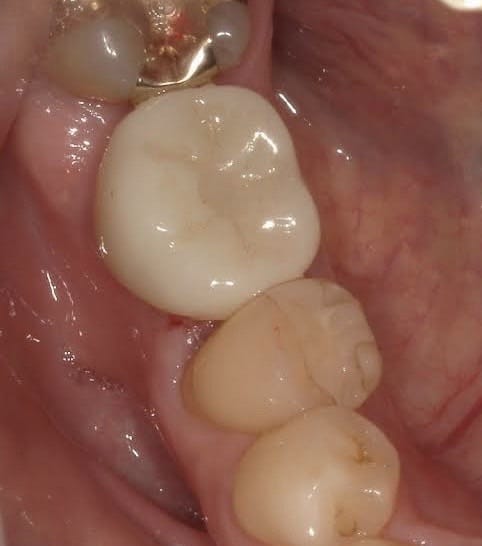

右の奥歯を過去に他院でインプラントをした方が、当院で左下や上の歯のインプラントをする為に転院してくださった患者様です。

インプラントは高額な治療ですが、どこの位置にどの角度で埋入するかが、とても大事というのがわかりやすかったので、患者様に投稿することをお願いして挙げさせていただきました。

インプラントを快適に長く使って頂くには、菌と力のコントロールが大事なのですが、前のものは位置が悪く、汚れも溜まりやすいし、咬む力も変な方向にかかってしまう仕上がりになっています。

被せ物のクオリティーもその歯科医院がどこの技工所にどのブランドで頼むかで全く変わってきます。

インプラントをご検討の方、すでに行った方は参考にしてください。